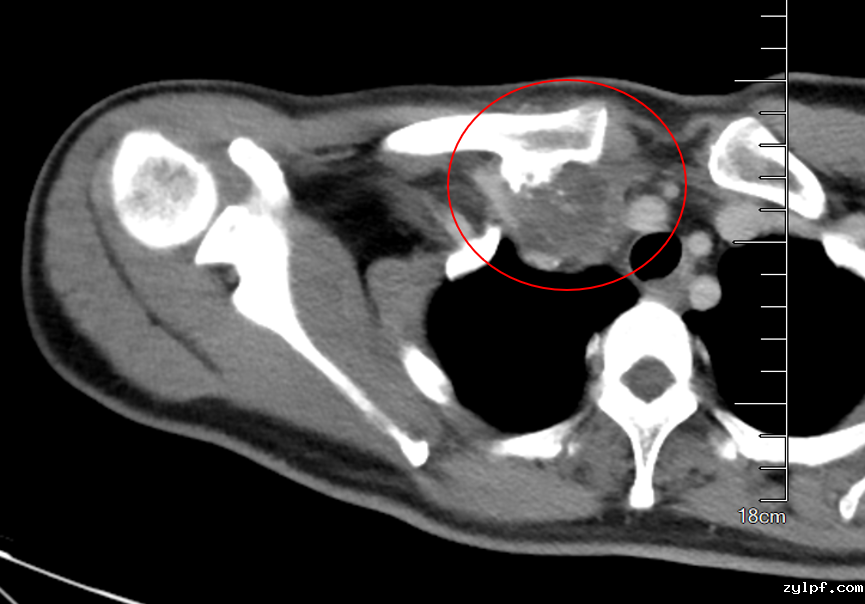

患者50岁女性,因体检发现右锁骨肿物10余天来诊。入院后X光片示右锁骨胸骨端膨大,密度减低,CT及MRI检查提示右侧锁骨局部骨性凸起伴周围肿块形成,考虑右锁骨胸骨端软骨肉瘤。

图片 1.png

完善术前评估及准备后,王伟东副主任团队为患者实施了右锁骨胸骨端继发型软骨肉瘤扩大切除术+自体腓骨移植重建术。术中见肿物与颈总动脉、头臂静脉相邻紧密,王伟东副主任凭借扎实的手术技术,完整将肿瘤和临近大血管分离,完整切除肿瘤。目前患者伤口恢复良好,已逐步开始康复锻炼,肩关节活动无障碍。